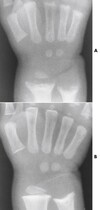

What pathology is this image showing?

Kid with rickets before and after vit. D supplements (in the top image-flatter looking)